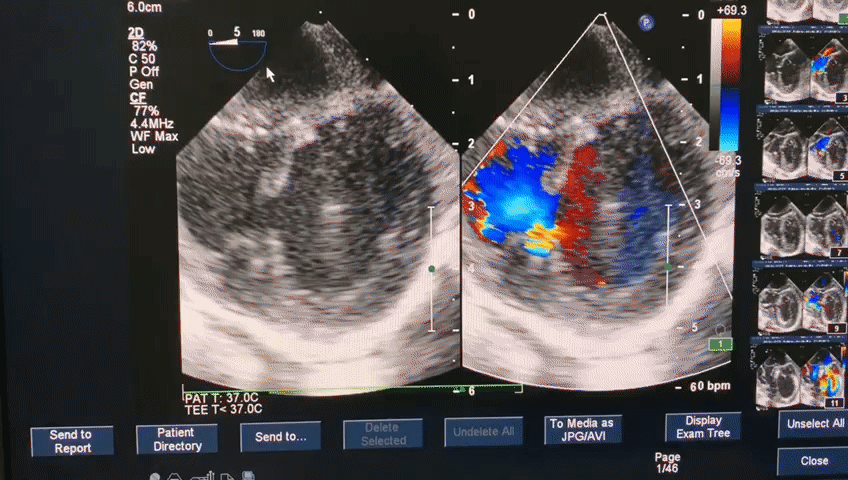

Операцию проводит бригада врачей под чреспищеводным эхокардиографическим (ЧП ЭХОКГ) контролем. После выполнения министернотомии используется пункция передней стенки правого желудочка.

В левый желудочек через ДМЖП вводится система доставки окклюдера. Затем производится последовательное открытия дистального и проксимального диска окклюдера. Таким образом, ДМЖП закрывается окклюдером, место прокола ПЖ ушивается, рана закрывается помощью косметической технологии.